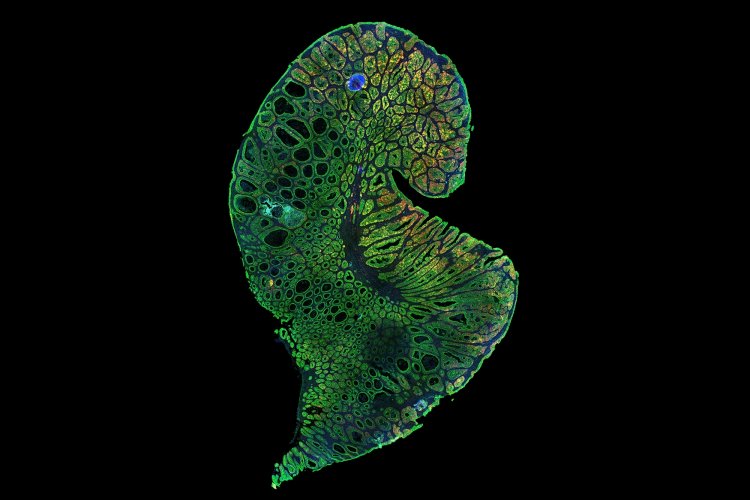

MIT Stem Cell Initiative studies focus on normal and cancer stem cells of epithelial tissues. Epithelia are one of four general tissue types in the body; they line most organs and are where the vast majority of cancers arise. Epithelial cells from different organs share some biological properties, but also have distinct differences reflecting the organ’s specific role and/or environment. In particular, the MIT Stem Cell Initiative has focused on the breast and colon, as these tissues are quite different from each other, yet each constitutes a major portion of cancer incidence.

New technologies are enabling the researchers to make significant headway in these investigations, progress that was not feasible just a few years ago. Specifically, they are using a combination of specially cultured cells, sophisticated and highly controllable mouse models of cancer, and single-cell RNA sequencing and computational analysis techniques that are uniquely suited to extracting a great deal of information from the relatively small number of stem cells.